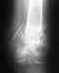

На представленном снимке, к сожалению, ничего обнадеживающего не видно, вполне ожидаемо несращение и вновь несостоятельность фиксации.

Решение есть только хирургическое - умело сделанный реостеосинтез с костной пластикой.